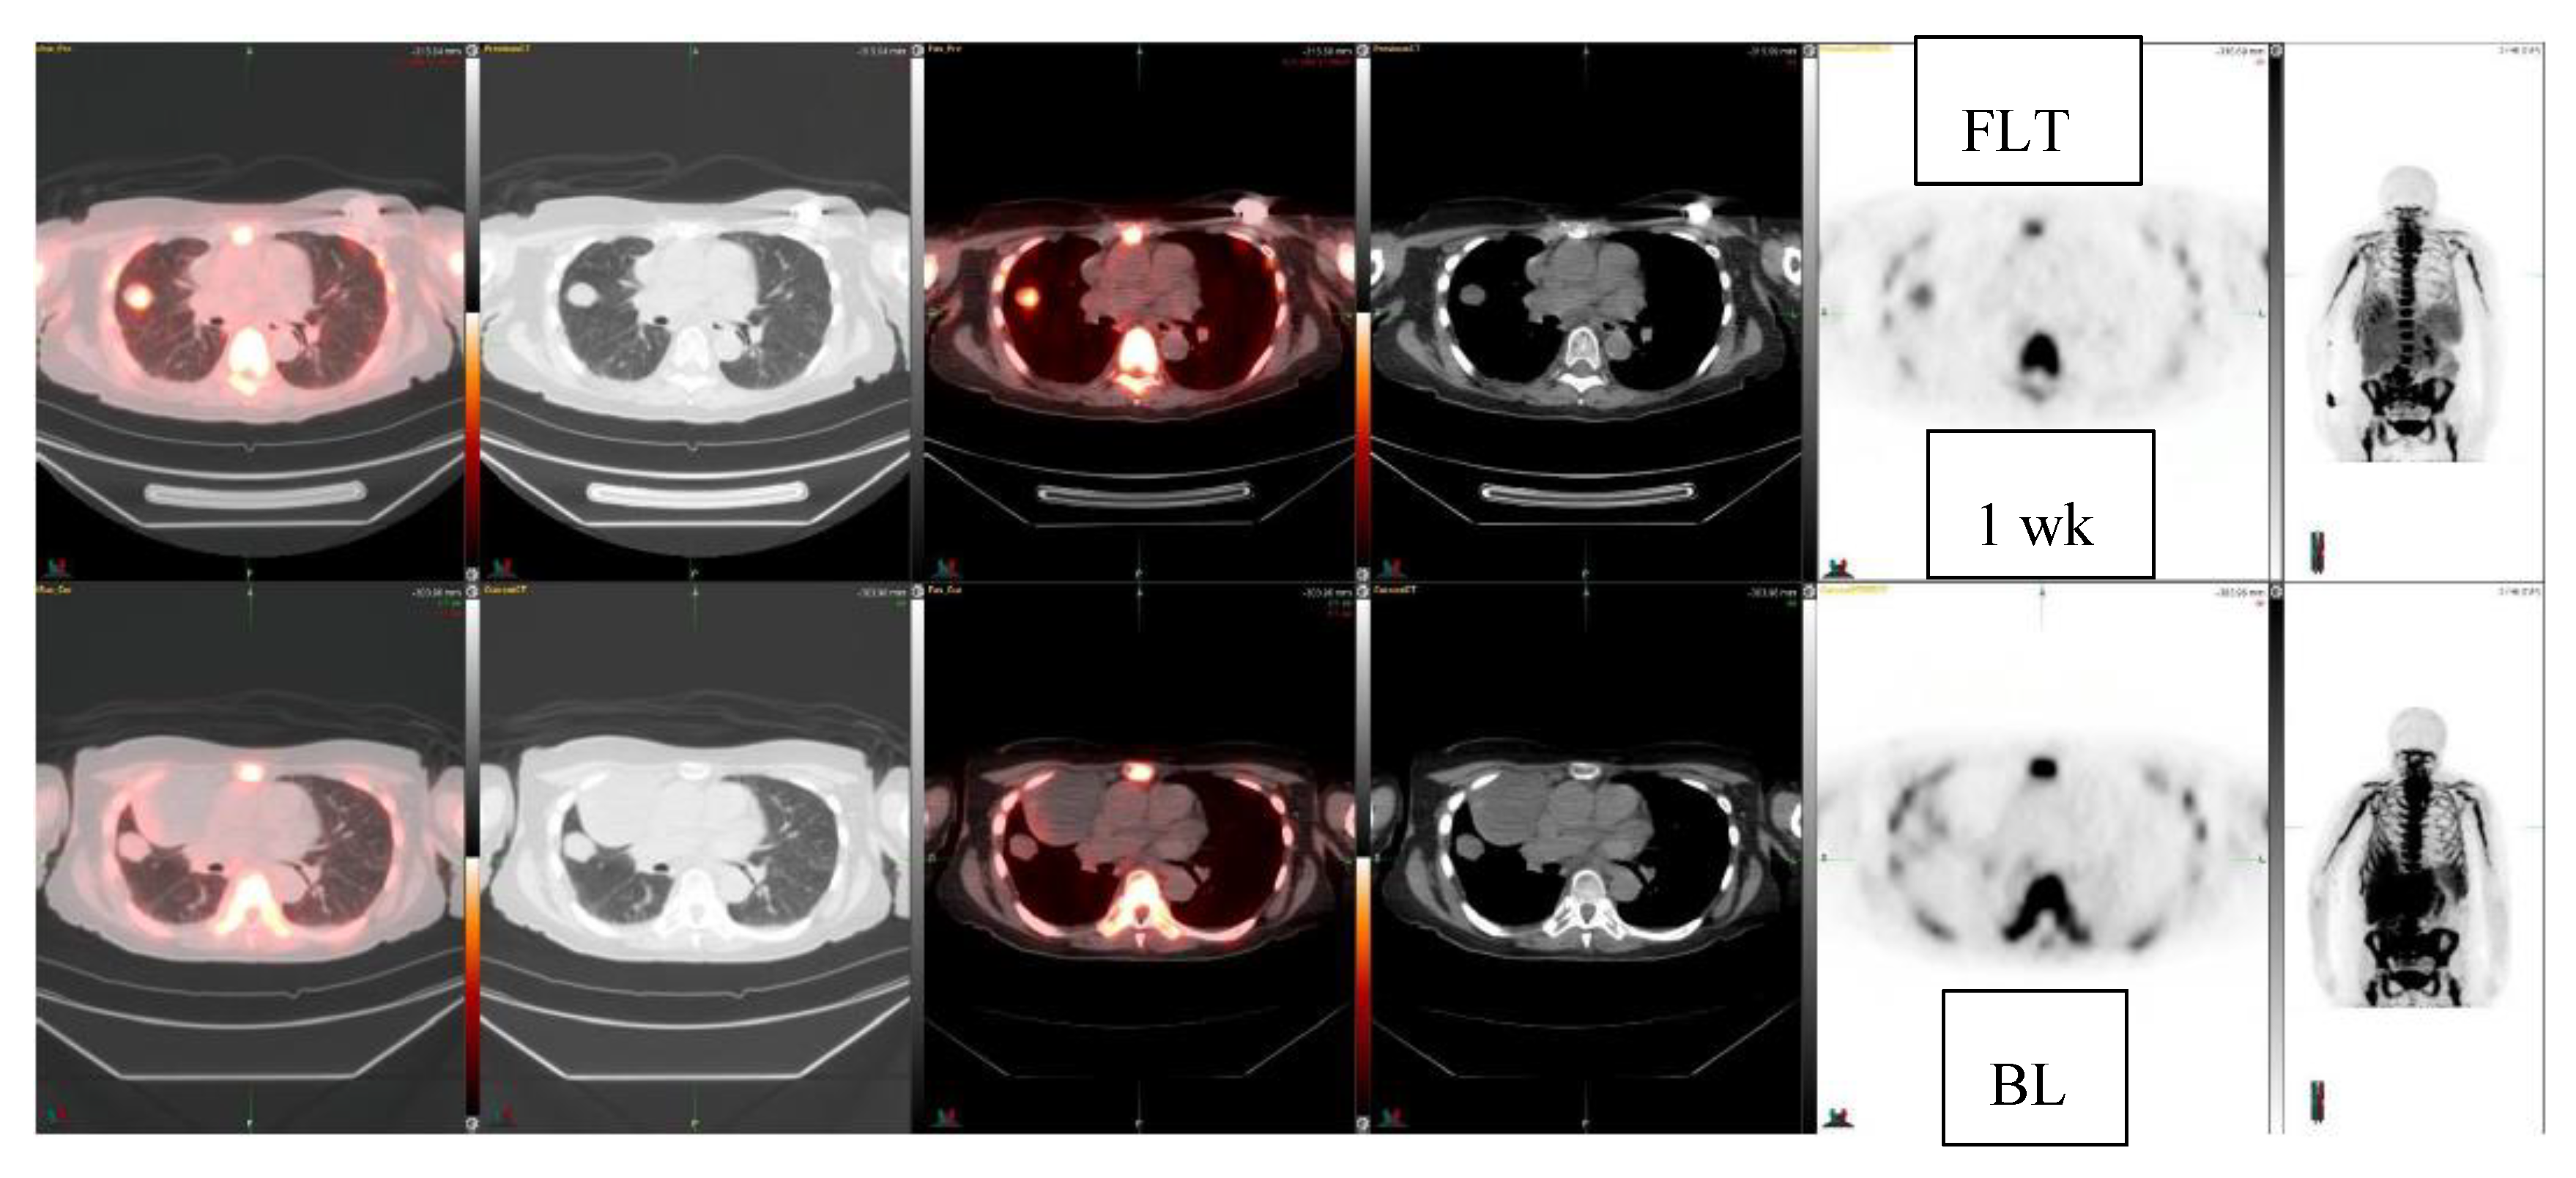

Figure 4.

Fibrous tumor, pleura. FLT-study at baseline and at 1 week (2 rows) demonstrates decrease (−43%) in the lung mass: FLT: SUVmax 3.0 ->1.7. On CT it becomes slightly bigger, CT: 2.4 cm × 1.9 cm ->2.5cm × 2.0 cm.

Next, 10 patients who were treated with c-met inhibitor (5 patients) or -2 inhibitor (5 patients) and had a total of 11 lesions were studied for early response with FLT (Table 2). They were studied at baseline and once after the initiation of the new therapy at 1–4 weeks. Five patients demonstrated FLT response, three patients had no change, and two patients progressed. Among these patients, two anecdotal patient cases are detailed in the figures. A patient with clear cell sarcoma of the left foot was studied at baseline and at one week with 18F-FLT and with 18F-FDG (Figure 3). This patient had a sub-carinal lymph node metastasis. With 18F-FLT, the outcome at one week was −13% (R), whereas 18F-FDG did not show any response +37%, and SUVmax increased from 8.9 to 12.2. On CT scans, the tumor was slightly larger: 2.2 cm × 1.2 cm →2.3 cm × 1.5 cm (Figure 3). In Figure 4, a patient with a fibrous tumor in pleura is shown, demonstrating a right lung mass. The patient was studied at baseline and at 1 week with 18F-FLT and the concentration decreased −43%. On CT, the tumor was slightly larger: 2.4 cm × 1.9 cm →2.5 cm × 2.0 cm (Figure 4).